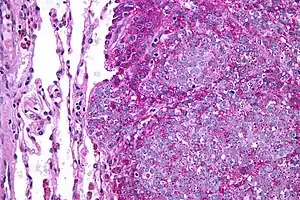

Na histologia, o sarcoma de Ewing é conhecido como um tumor de pequenas células redondas e azuis. Geralmente aparece como uma saliência no osso, detectada por meio de biópsias. Se apresentam como dolorosas massas crescentes e o local afetado frequentemente é sensível, quente e edemaciado. Alguns pacientes apresentam achados sistemicos, incluindo febre, elevação da velocidade de hemossedimentação, anemia e leucocitose, que mimetizam uma infeção.

É um tumor positivo para o marcador CD99 e negativo para o CD45.[9]